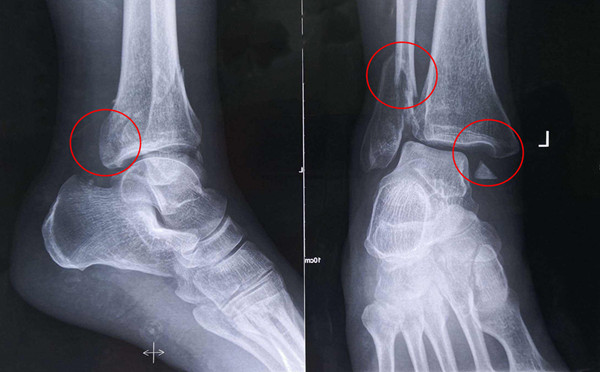

踝關(guān)節(jié)骨折在X影像上的表現(xiàn)有很多種。如內(nèi)踝骨折和外踝骨折,我們可以在影像上看到骨折處的骨折線是不連續(xù)的。還有后踝的骨折,內(nèi)踝、外踝、后踝聯(lián)合在一起發(fā)生的骨折,我們稱之為“三踝骨折”,這些都是在X影像上能夠顯示出來的。

內(nèi)踝骨折

外踝骨折

后踝骨折

三踝骨折